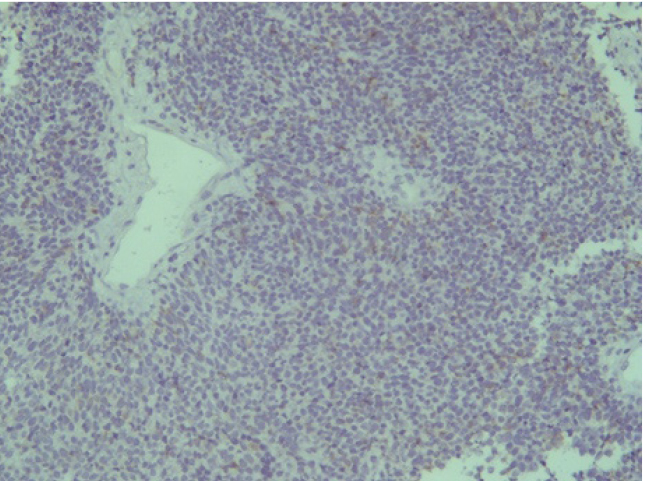

Отрицательная экспрессия была отмечена в диагностических образцах с использованием антител к Keratin.Pan, CD45, p63, S100, EMA (E29), TTF1(рис. 7–12).

Рис. 7. Keratin.Pan [AE/AE3] ×200

Рис. 8. CD 45 [Cocktail] ×200

Рис. 9. p63 [7JUL] RTU ×200

Рис. 10. S100 ×200

Рис. 11. EMA [E29] ×200

Рис. 12. TTF1 [8G7G3/1] ×200